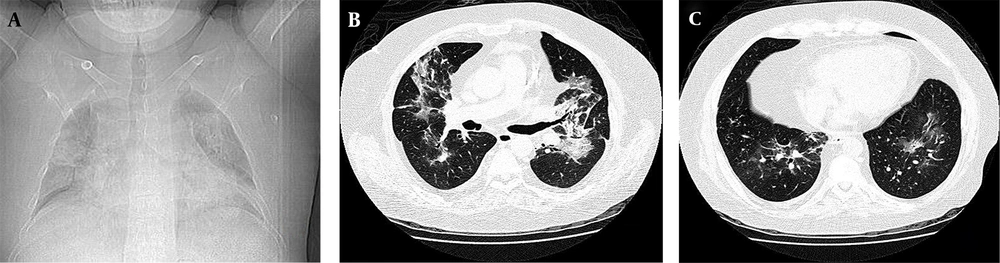

The 45-year-old patient was admitted in a specialized hospital in Tehran with loss of consciousness and symptoms of apnea due to hypoxia. Upon admission, the patient suffered from edema of the hands and legs accompanied with ataxia and low-grade fever. In physical examination, patient was tachypneic. In lung auscultation, fine crackles were remarkable especially in bases of both lungs. In initial examination, the patient’s spouse stated a history of cough and apnea from 10 days ago, aggravated in the last week. The coughs were dry and nonprovocative, and mixed with sputum and blood two days before admission to the hospital. The patient was cytomegalovirus (CMV)-positive with a history of kidney transplant 24 years ago, and had not received any prophylaxis against opportunistic infections. Furthermore, the medical record of the patient indicated a history of receiving three immunosuppressive drugs including cyclosporine, azathioprine and prednisolone after renal transplantation. Chest X-ray (CXR) showed diffuse bilateral perihilar opacity with extension to periphery of upper and lower lobes (Figure 1A). CT section images showed bilateral perihilar alveolar ground glass opacity with extension to periphery of upper and lower lobes. No evidence of cavitation, pleural effusion, abscess formation or adenopathy was observed (Figures 1B and 1C). In further studies, ultrasound of the body showed tense ascites in the abdominal region and an echogenic nodule 17 mm in diameter in the left lobe of the liver. In the laboratory setting, white blood cell (WBCs) and red blood cells (RBCs) counts were reported as 8.2 thous/cumm and 4.15 mL/cumm, respectively. The polymorphonuclear (PMN) cells count was remarkably increased (≈96%). Serum level of sodium and potassium was measured as 136 mEq/L and 5.4 mEq/L respectively, in which the serum level of potassium was higher than the standard values. The values of lactate dehydrogenase (LDH), C-reactive protein (CRP) and erythrocyte sedimentation rate (ESR) are presented in the Table 1. All three reported values were greater than standard. On the fifth day of hospitalization, the patient developed worsening shortness of breath and inability to lie down, and the arterial O2 was 69%. The patient was transferred to the intensive care unit; intubation was performed and the patient was connected to mechanical ventilation (MV). The lung lavage sample was positive for Pneumocystis jiroveci using gomori methenamine silver staining (Figure 2A).